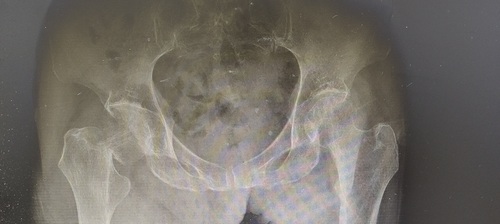

经我院检查,发现导致卢老太卧床不起的罪魁祸首原来是右侧股骨颈骨折了,可把家里人急坏了,心里想着“那老太太完了,走不了路那就没几天好活了不是”